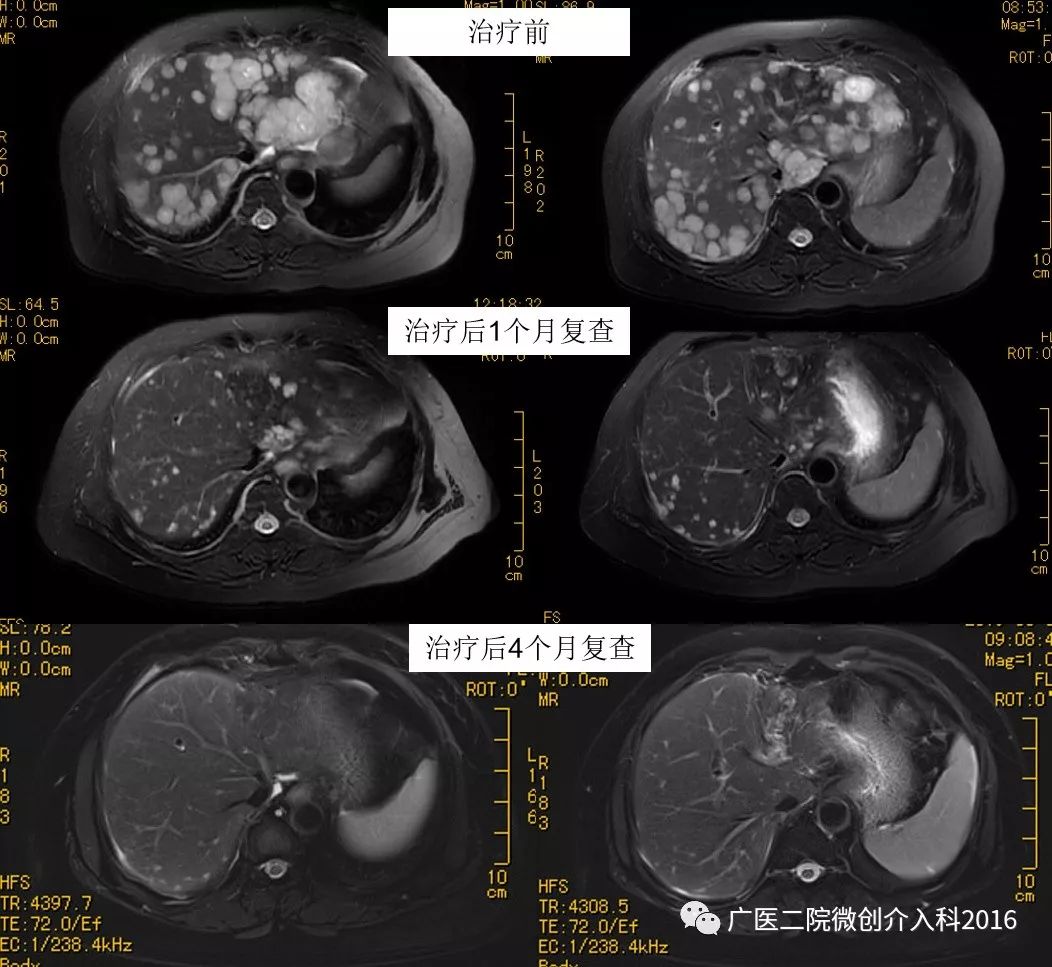

男性,52岁,鼻咽癌并肝内多发转移,既往行多次放疗、化疗、靶向治疗,鼻咽病灶控制良好,但肝内转移瘤病灶不断进展。辗转多家医院就诊,无特别有效的治疗方法。后到我科就诊,行肝动脉灌注化疗+ PD-1免疫治疗,治疗后1个月复查肝内肿瘤明显缩小、消失,治疗后4个月复查肝内肿瘤基本消失!

专家点评

该患者为鼻咽癌肝转移,经过多次放、化疗,虽然鼻咽部肿瘤得到控制,但是多发肝转移的出现给予患者沉重的打击,精神崩溃。我们采取了肝动脉持续灌注治疗的方法联合了pd-1免疫治疗,显示了良好的近期效果,给予了患者对治疗的信心,生存延长。